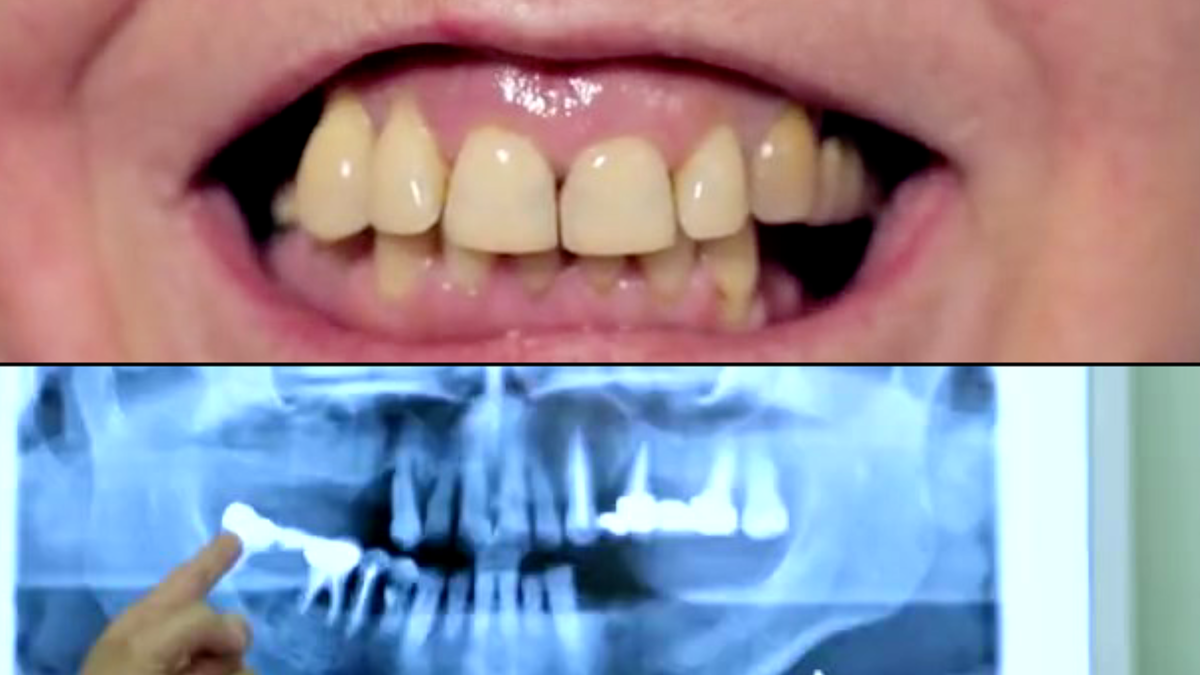

Зубы Ксении Стриж

У женщины была катастрофическая ситуация с зубами. Ей удалили все старые зубки под мостами, и на верхней челюсти осталось всего три зуба. Затем ей сделали костную пластику и поставили 11 имплантов.

Многим зрителям передачи не понравилось, как стоматолог сделал Ксении зубы.

— Зубы сделали неудачные: белые, ровные, но неестественные. Такое ощущение, что они Ксении мешают.

— Зачем так делать зубы, чтоб видны были за километр! Бедная Ксения не знает, как с такими зубами говорить нормально!

— Зубы Ксении выглядят так, как будто прикус неправильный.

— Зубы, как у бобра... Зачем такие огромные? Ей даже трудно разговаривать.

Но Ксения объяснила, что за неё переживать не стоит: "У меня времёнки (временные зубы). Импланты приживаются долго, поэтому всем сначала ставят временные на случай отторжения. Они вполне носибельные, но есть и покрепче, и подороже материал."